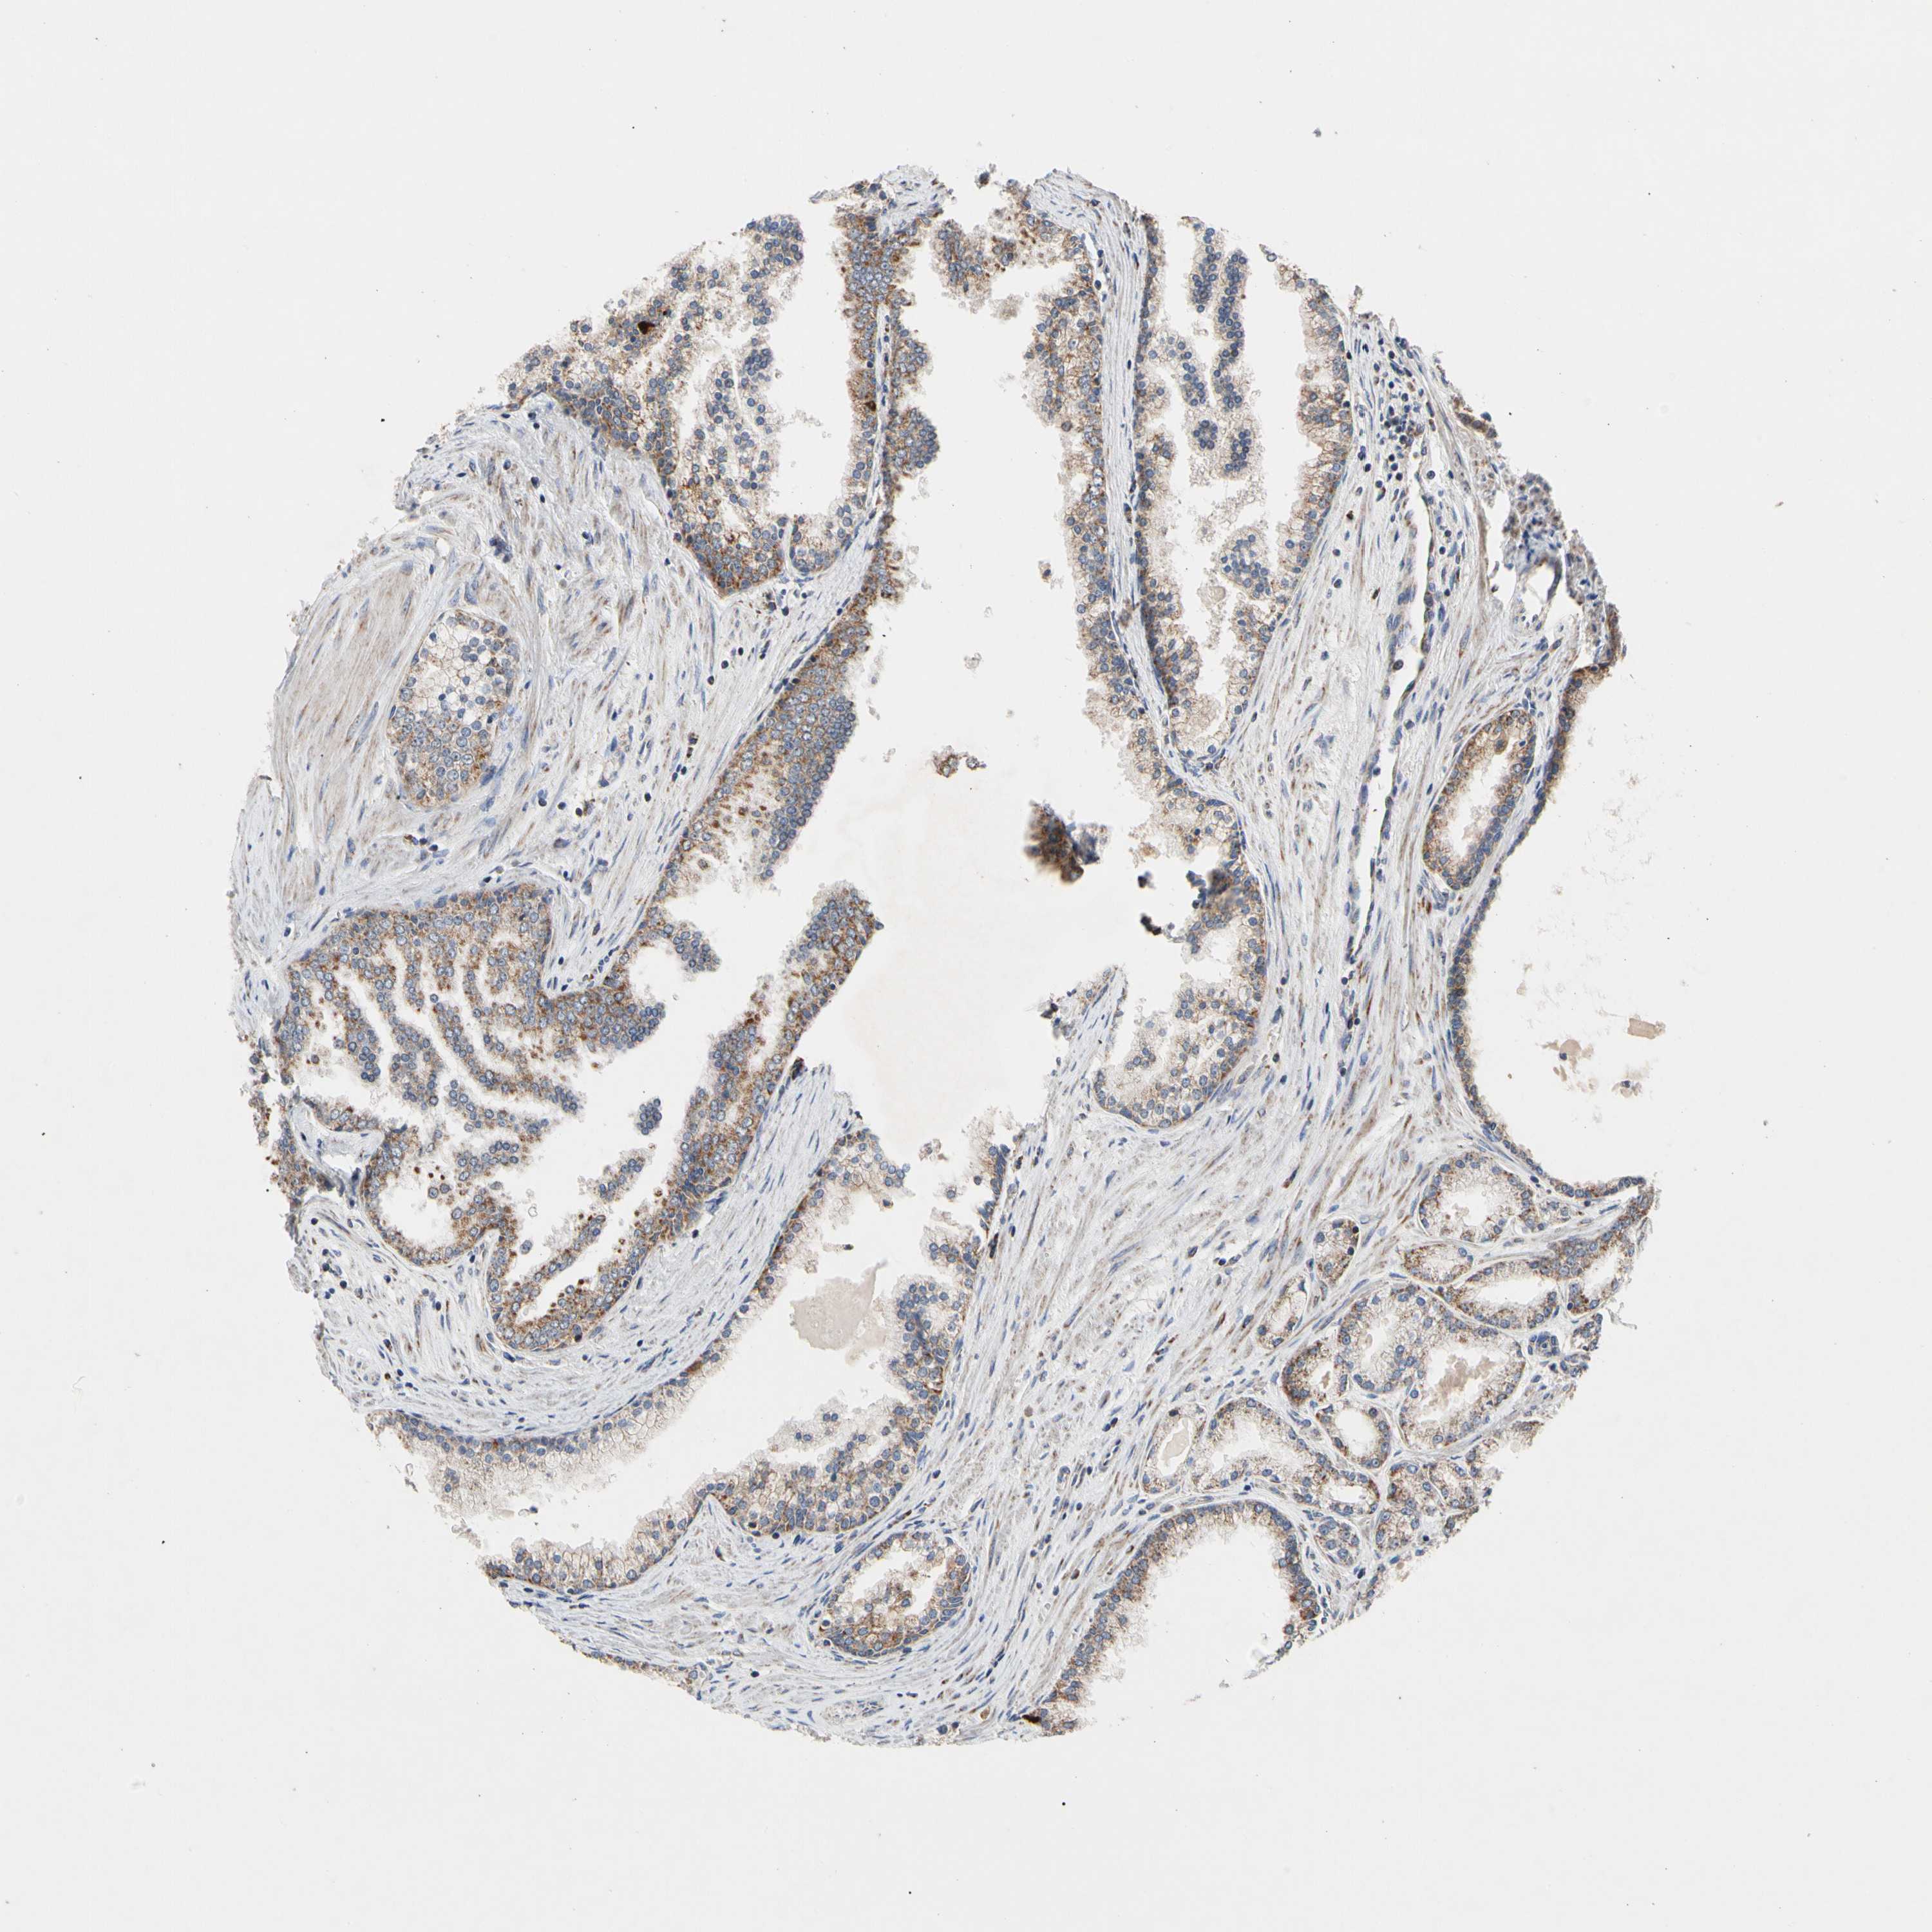

PROSTATE CANCER - Protein expressioni

A mouse-over function shows sample information and annotation data. Click on an image to view it in a full screen mode. Samples can be filtered based on level of antibody staining by selecting one or several of the following categories: high, medium, low and not detected. The assay and annotation is described here.

Note that samples used for immunohistochemistry by the Human Protein Atlas do not correspond to samples in the TCGA dataset.

Antibody stainingi

Antibody staining in the annotated cell types in the current human tissue is reported as not detected, low, medium, or high, based on conventional immunohistochemistry profiling in selected tissues. This score is based on the combination of the staining intensity and fraction of stained cells.

Each image is clickable and will lead to virtual microscopy that enables deeper exploration of all samples and also displays staining intensity scores, fraction scores and subcellular localization as well as patient and tissue information for each sample.

Antibody HPA008012

Antibody HPA045506

Staining

High

Medium

Low

Not detected

Intensity

Strong

Moderate

Weak

Negative

Quantity

>75%

75%-25%

<25%

None

Location

Nuclear

Cytoplasmic/membranous

Cytoplasmic/membranous,nuclear

Adenocarcinoma, Low grade

Adenocarcinoma, High grade